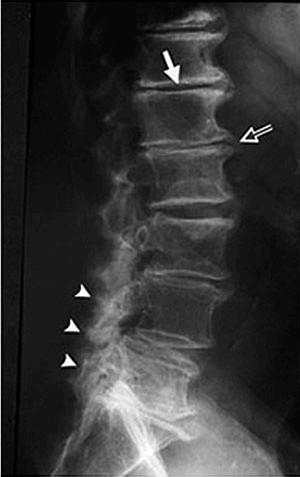

Past injury or just hard work over the years can cause painful arthritis. Your joints start to not move properly and are put in a faulty position. Your body recognizes this and tries to help. You will see this on an X-Ray clearly. Let’s check out a list below:

Space in between joints and vertebra are shrinking

Normal areas of the spine or pelvis will look different than the involved areas.

Calcium build up around involved areas will be visual.

The structure of your spine and pelvis will not be in their right position. You could see this as the neck bending forward or your pelvis higher on one side.